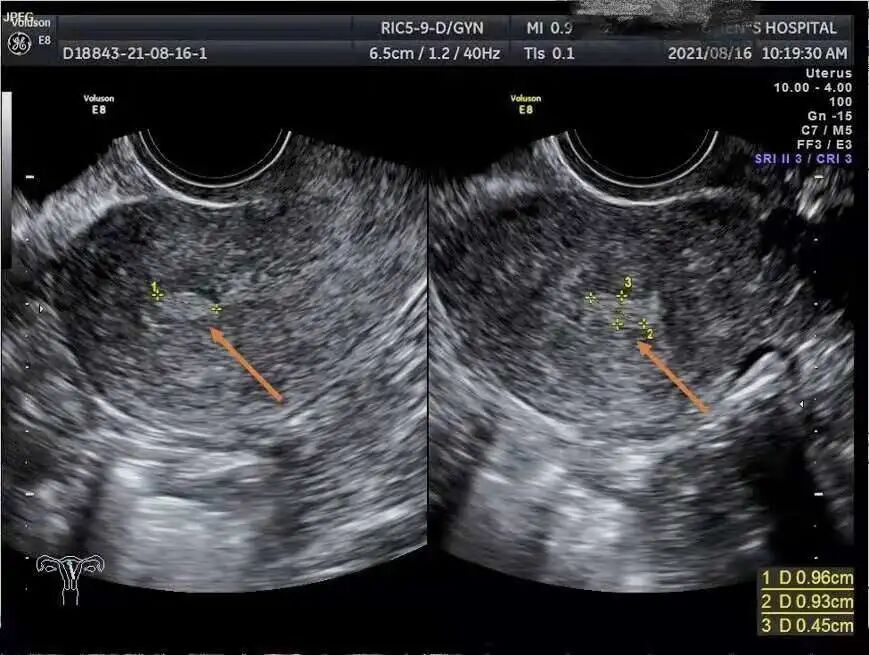

子宫内膜息肉是子宫局部内膜过度生长,数量可能是一个,也可能是多个,个头也是有大有小;分无蒂或有蒂,息肉由子宫内膜腺体,间质和血管组成。

虽然临床上95%的子宫内膜息肉都是良性的,直径不会大于1cm。

①B超检查:B超检查是检查宫腔、盆腔病变主要体检手段之一,绝大部分子宫内膜息肉能够被发现。

②宫腔镜检查:宫腔镜检查被认为是诊断子宫内膜息肉的 “金标准”,并能直观息肉位置、大小、数目及宫腔情况,还能进行有效治疗。